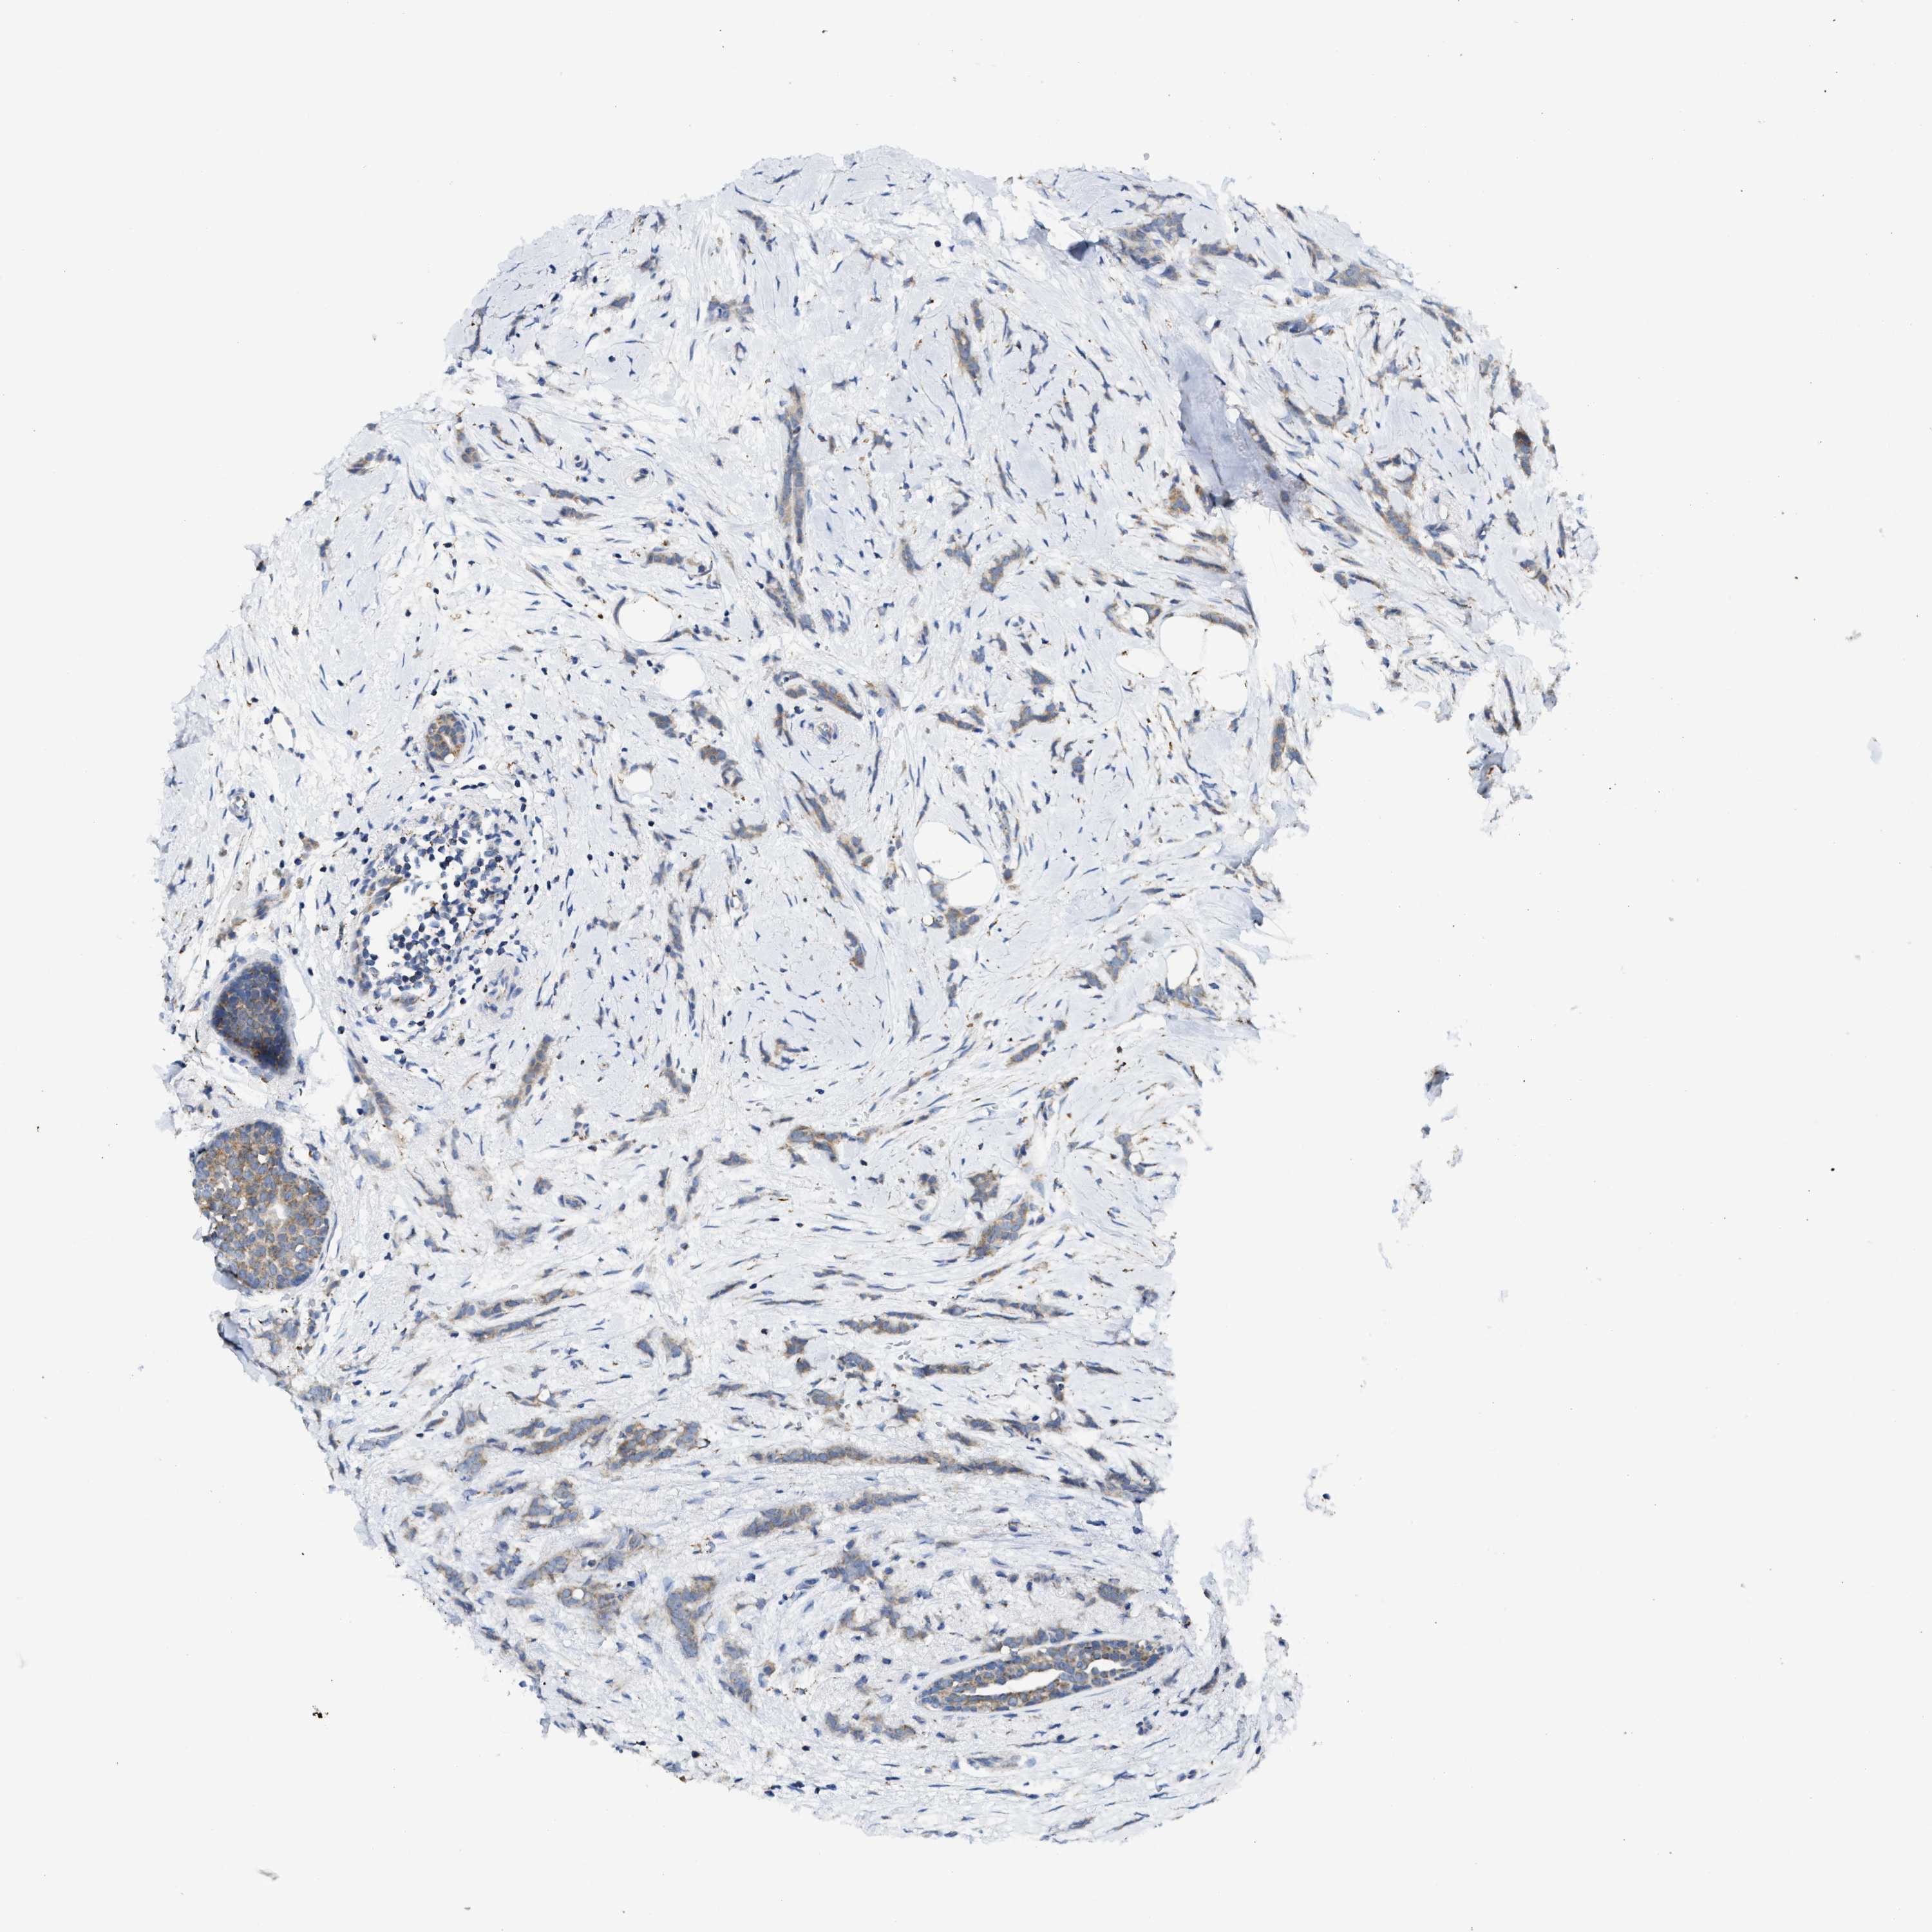

CANCER BREAST CANCER Show tissue menu

BRCA TCGA BRCA VALIDATION PROTEIN EXPRESSION

ANTIBODIES

AND

VALIDATION